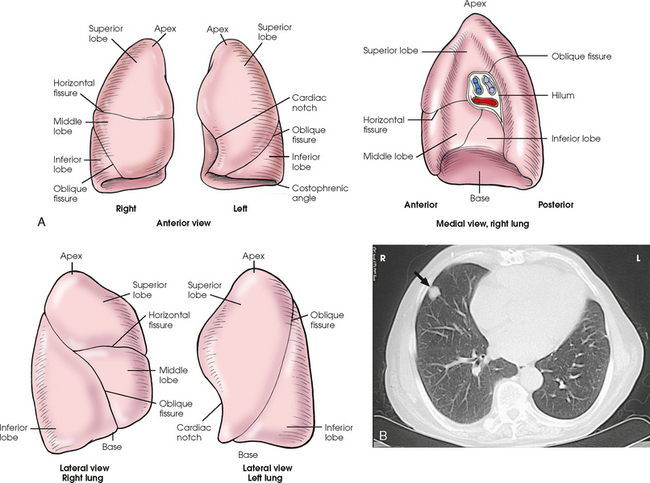

The lungs are the organs of respiration (Fig. 10-4). They are the mechanism for introducing oxygen into the blood and removing carbon dioxide from the blood. The lungs are composed of a light, spongy, highly elastic substance, the parenchyma, and they are covered by a layer of serous membrane. Each lung presents a rounded apex that reaches above the level of the clavicles into the root of the neck and a broad base that, resting on the obliquely placed diaphragm, reaches lower in back and at the sides than in front. The right lung is about 1 inch (2.5 cm) shorter than the left lung because of the large space occupied by the liver, and it is broader than the left lung because of the position of the heart. The lateral surface of each lung conforms with the shape of the chest wall. The inferior surface of the lung is concave, fitting over the diaphragm, and the lateral margins are thin. During respiration, the lungs move inferiorly for inspiration and superiorly for expiration (Fig. 10-5). During inspiration, the lateral margins descend into the deep recesses of the parietal pleura. In radiology, this recess is called the costophrenic angle (see Fig. 10-5, B). The mediastinal surface is concave with a depression, called the hilum, that accommodates the bronchi, pulmonary blood vessels, lymph vessels, and nerves. The inferior mediastinal surface of the left lung contains a concavity called the cardiac notch. This notch conforms to the shape of the heart.

Fig. 10-5 A, Movement of lungs during inspiration and expiration. B, Costophrenic angles shown (arrows) on PA projection of chest.